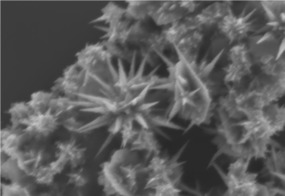

Ученые из Национального технологического университета «МИСиС» (Москва, Россия) совместно с коллегами из Института ядерной физики имени Саха (Калькутта, Индия) смогли синтезировать стабильные золотые наночастицы в форме звезд для борьбы с онкологическими заболеваниями. Недорогие и нетоксичные наночастицы позволят эффективно диагностировать рак на ранних стадиях и точечно уничтожать пораженные клетки. Результаты исследования опубликованы в научном издании Journal of the Chemical Society.

Сегодня в медицине активно используются плазмонные наноматериалы на основе серебра и золота. «Плазмонными» называют наноструктуры, необычные оптические и физические свойства которых обусловливаются прежде всего их формой и структурой, а также колебанием свободных электронов внутри них. То, каким образом происходит это колебание, сильно зависит от формы и размера наночастиц. Именно это позволяет им иметь набор необычных оптических и физических свойств.

Работа над технологией проводилась при участии специалистов Российского онкологического центра имени Н.Н. Блохина. Сейчас ученые работают над улучшением частиц — пытаются синтезировать другие типы звезд.